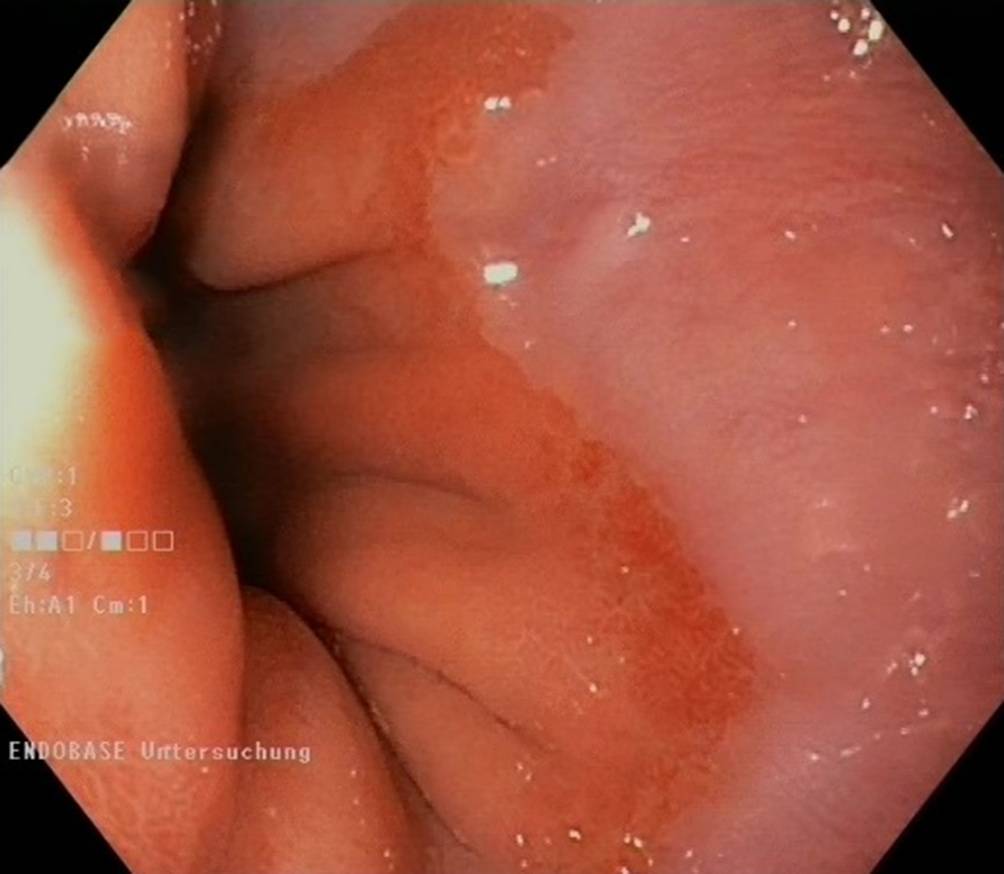

Mit zur Hilfenahme virtueller als auch analoger Additive wie systemadaptierte chromoendoskopische Verstärker (NBI® etc.) als auch chromoendoskopische Verstärker wie Essigsäure oder auch Färbelösungen wie Toluidinblau etc. konnte eine weitere Zunahme von Dysplasiearealen (Abb. 4) gezeigt werden [2528].

Abb. 4

Typisches Bild eines Short-Barrett-Ösophagus mit hochgradig verdächtigen Dysplasiearealen (zukünftige „routinemäßige“ KI-Indikation). (© Dr. Grade, selbst am CQK durchgeführte Endoskopie)